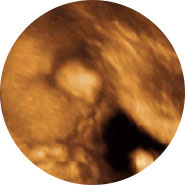

四维彩超能多方位、多角度、立体显示胎儿生长发育情况,为早期诊断胎儿先天性体表畸形如唇裂,脊柱裂,大脑、肾、心脏、骨骼发育不良等,和先天性心脏疾病提供全面的科学依据。

无脑儿

它不存在射线、光波和电磁波等辐射,对宝宝和孕妇健康没有任何影响。图像质量卓越,准确率高。

4D超声能自动多角度地观察胎儿,为早期诊断体表畸形提供科学依据。